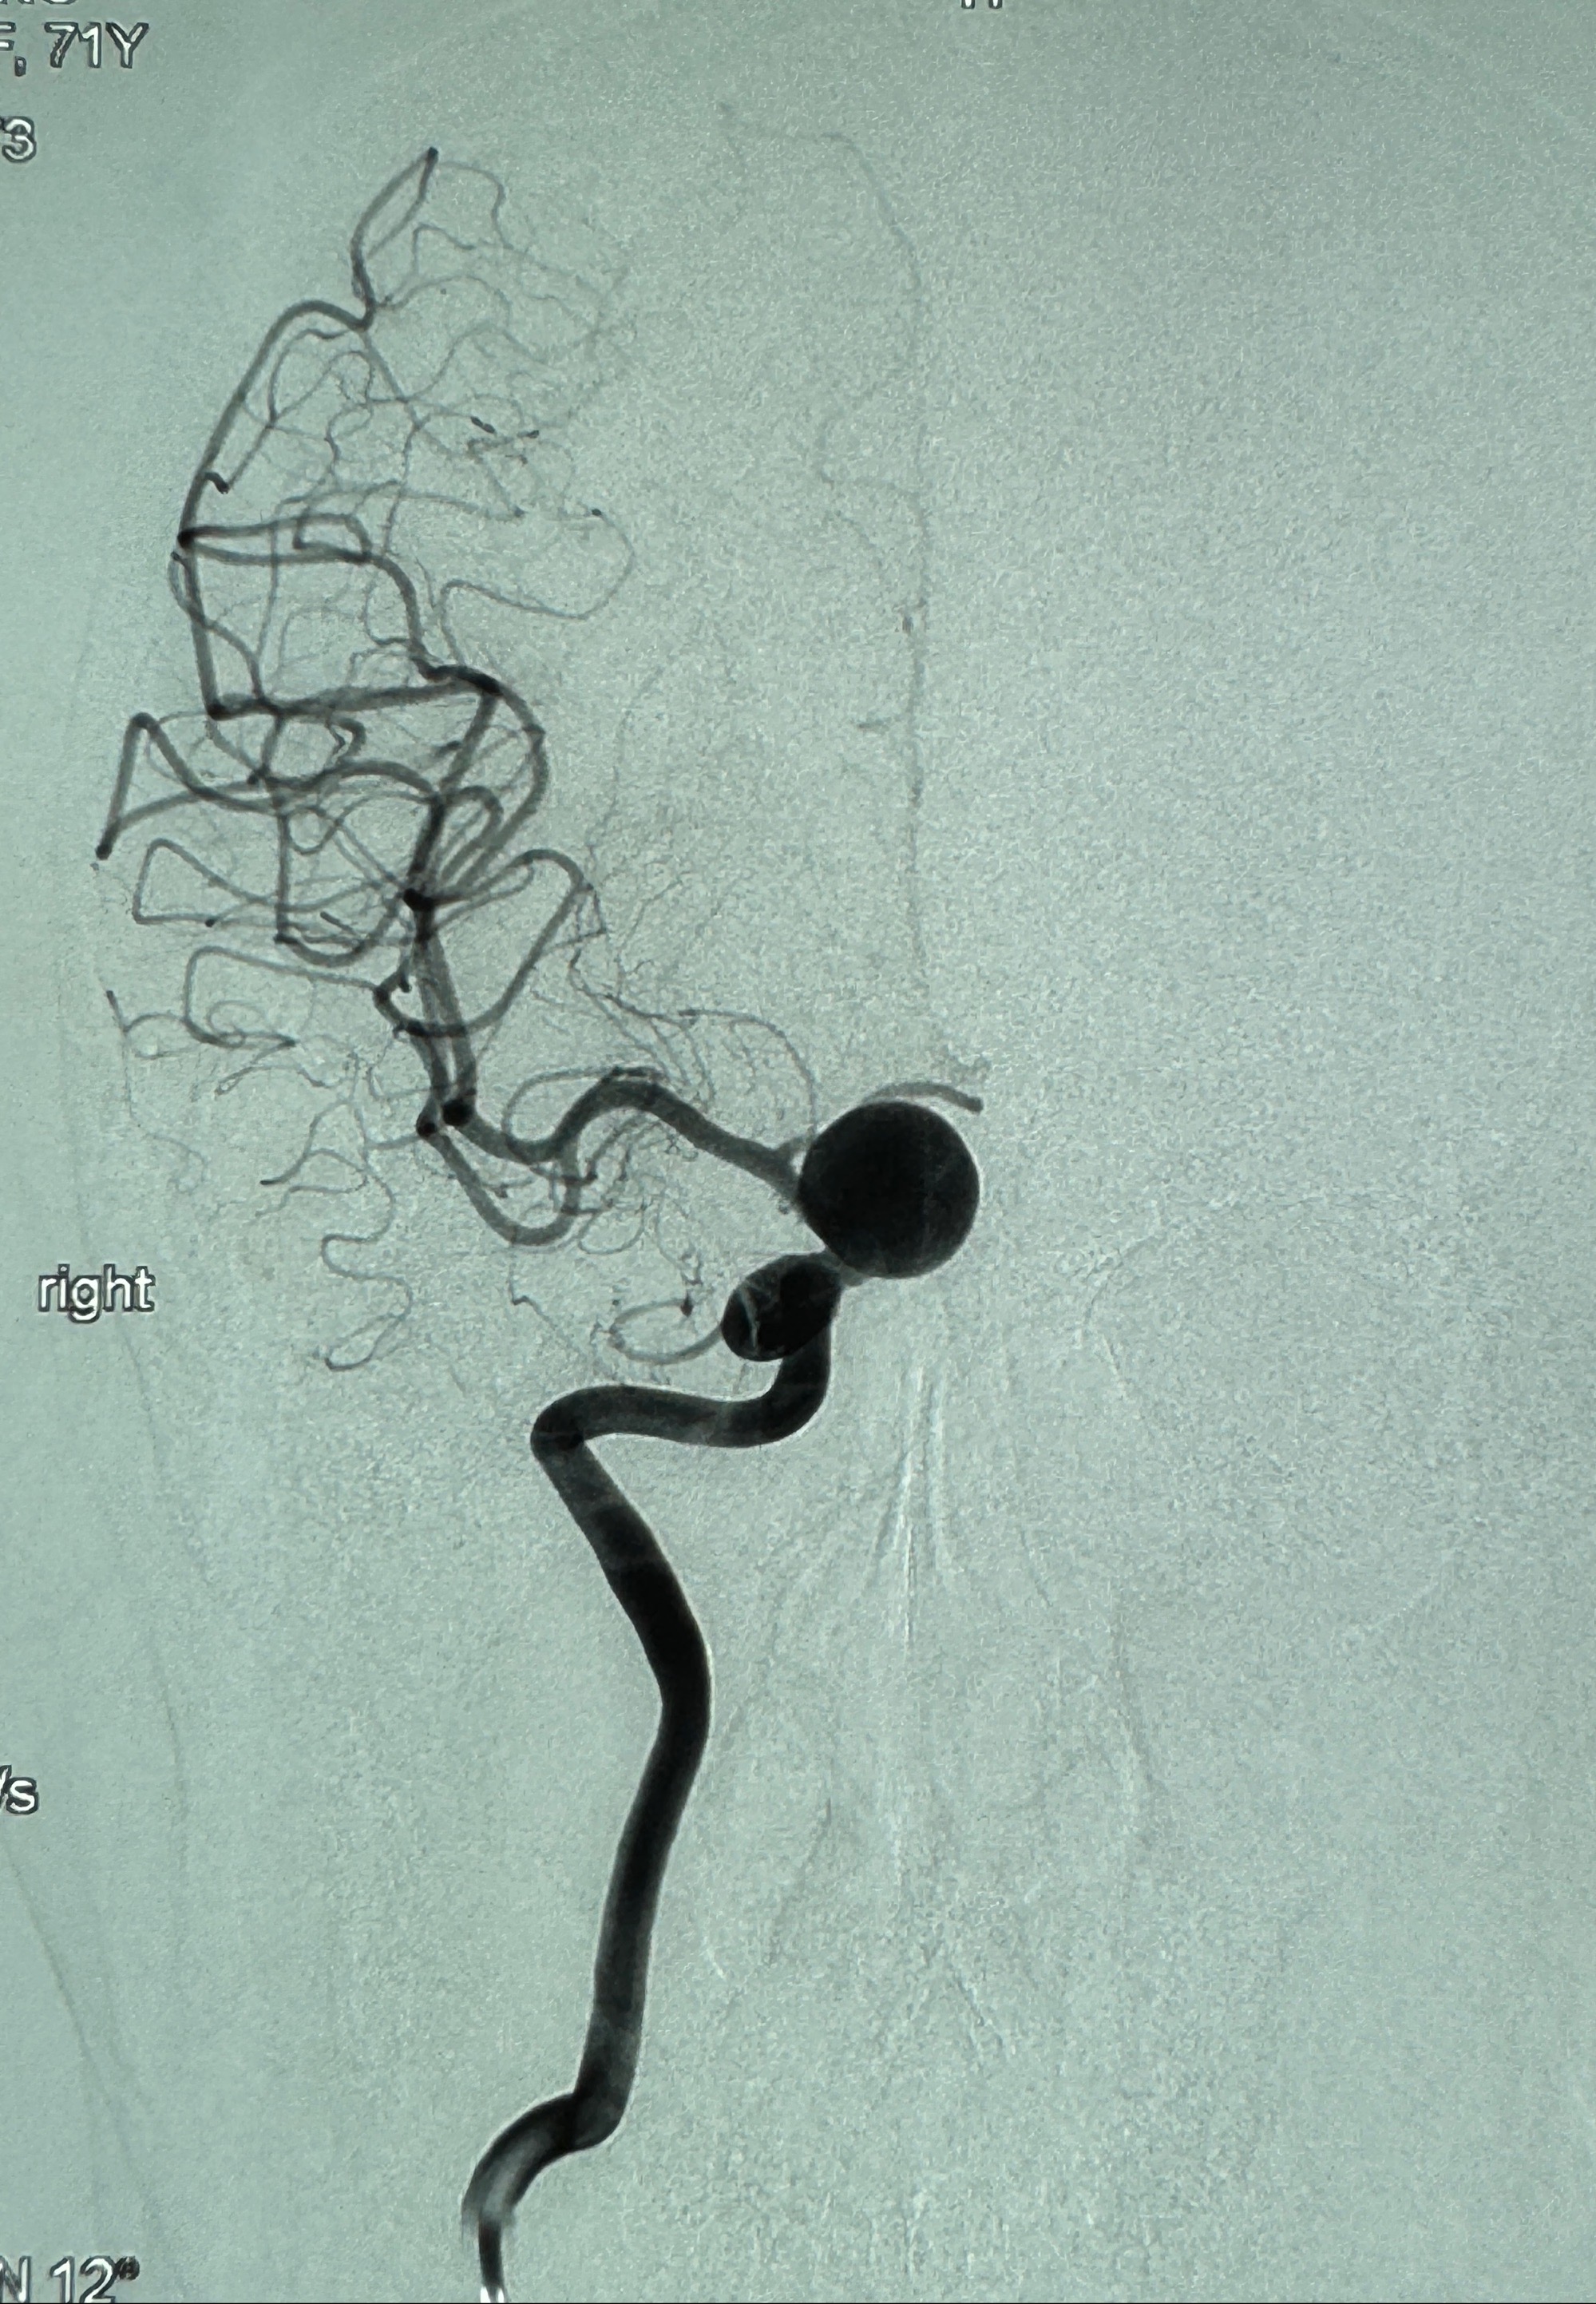

2023-12-27术后第十天复查DSA

支架贴壁佳,但可见射流,咋办?

2024-01-08全麻下再行植入密网支架一枚

Tubridge 4.5-35mm

支架植入顺利,贴壁佳,支架内血流通畅,动脉瘤内血液滞留明显